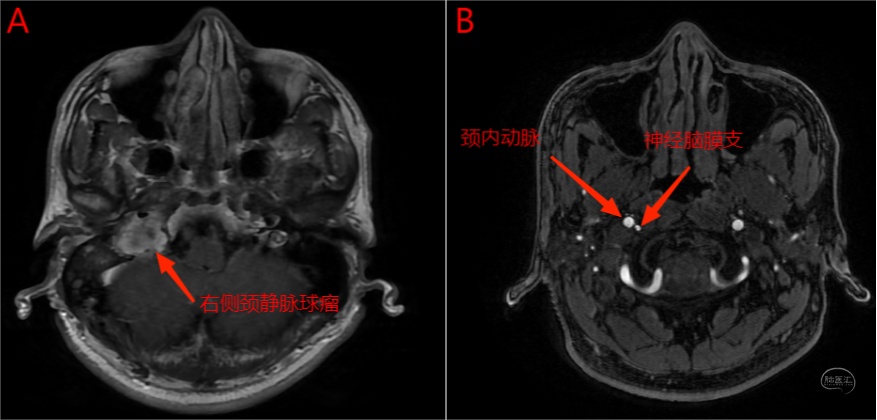

右侧颈静脉球瘤患者进行术前造影及栓塞,咽升动脉神经脑膜支(颈静脉孔支)为主要供血动脉。

图16 A图为轴位增强MRI,显示右侧颈静脉孔内病变强化明显;B图为TOF轴位图像,右侧咽升动脉神经脑膜支位于右侧颈内动脉后内侧,管径明显增粗(左侧显示不清)。